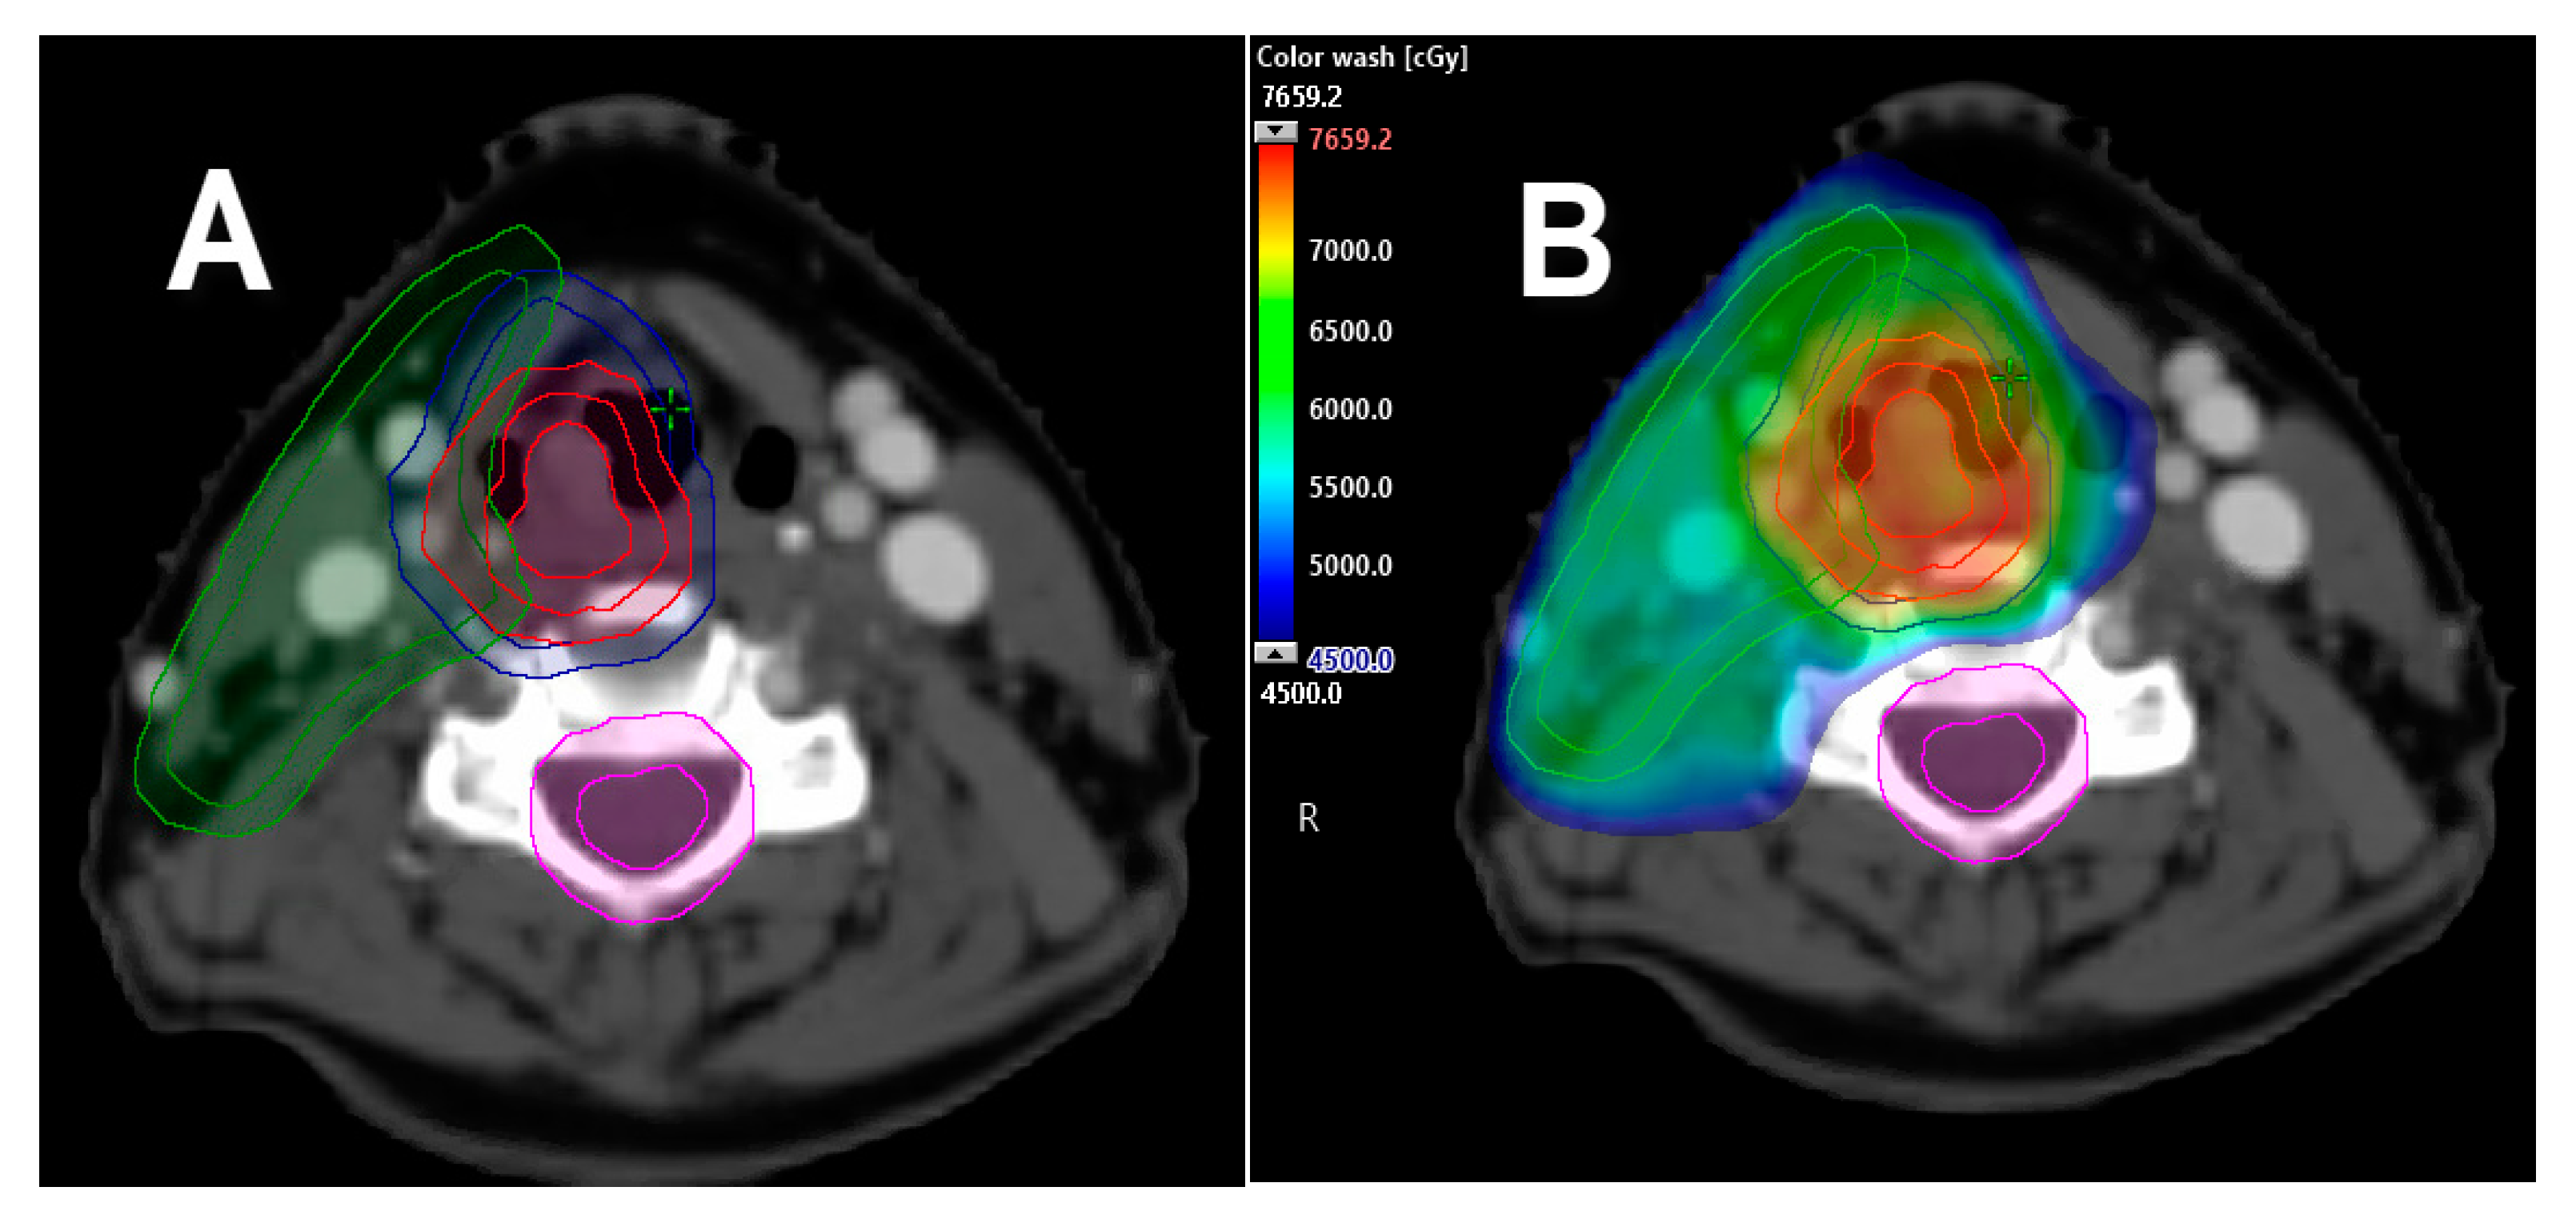

- Gamez, M.E.; Halyard, M.Y.; Hinni, M.L.; Hayden, R.E.; Nagel, T.H.; Vargas, C.E.; Wong, W.W.; Curtis, K.K.; Zarka, M.A.; Ma, D.; et al. Mucosal sparing radiation therapy in resected oropharyngeal cancer. Ann. Otol. Rhinol. Laryngol. 2017, 126, 185–191. [Google Scholar] [CrossRef]

- Swisher-McClure, S.; Lukens, J.N.; Aggarwal, C.; Ahn, P.; Basu, D.; Bauml, M.; Brody, R.; Chalian, A.; Cohen, R.B.; Fotouhi-Ghiam, A.; et al. A phase 2 trial of alternative volumes of oropharyngeal irradiation for de-intensification (AVOID): Omission of the resected primary tumor bed after transoral robotic surgery for human papilloma virus-related squamous cell carcinoma of the oropharynx. Int. J. Radiat. Oncol. Biol. Phys. 2020, 106, 725–732. [Google Scholar] [CrossRef]